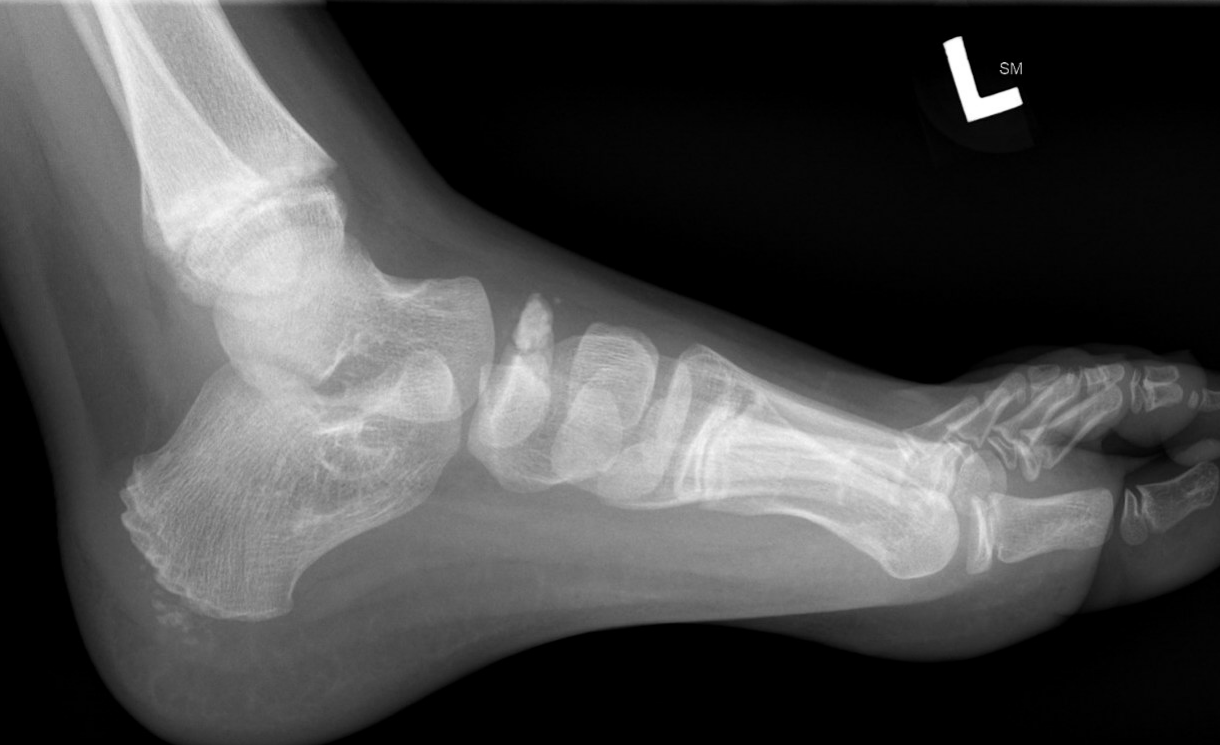

X-ray

Flattening / sclerosis / fragmentation of navicular